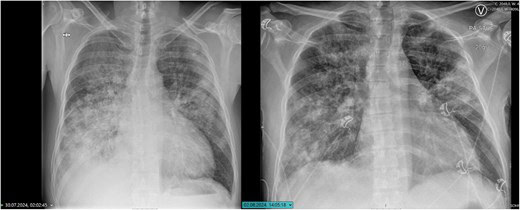

Radiografías de tórax desde la admisión inicial (izquierda) y la reingreso (derecha). La imagen inicial muestra amplias consolidaciones bilaterales consistentes con neumonía grave y derrame pleural. En la readmisión, hay una consolidación bilateral persistente pero ligeramente mejorada, lo que indica una resolución parcial de los infiltrados pulmonares.